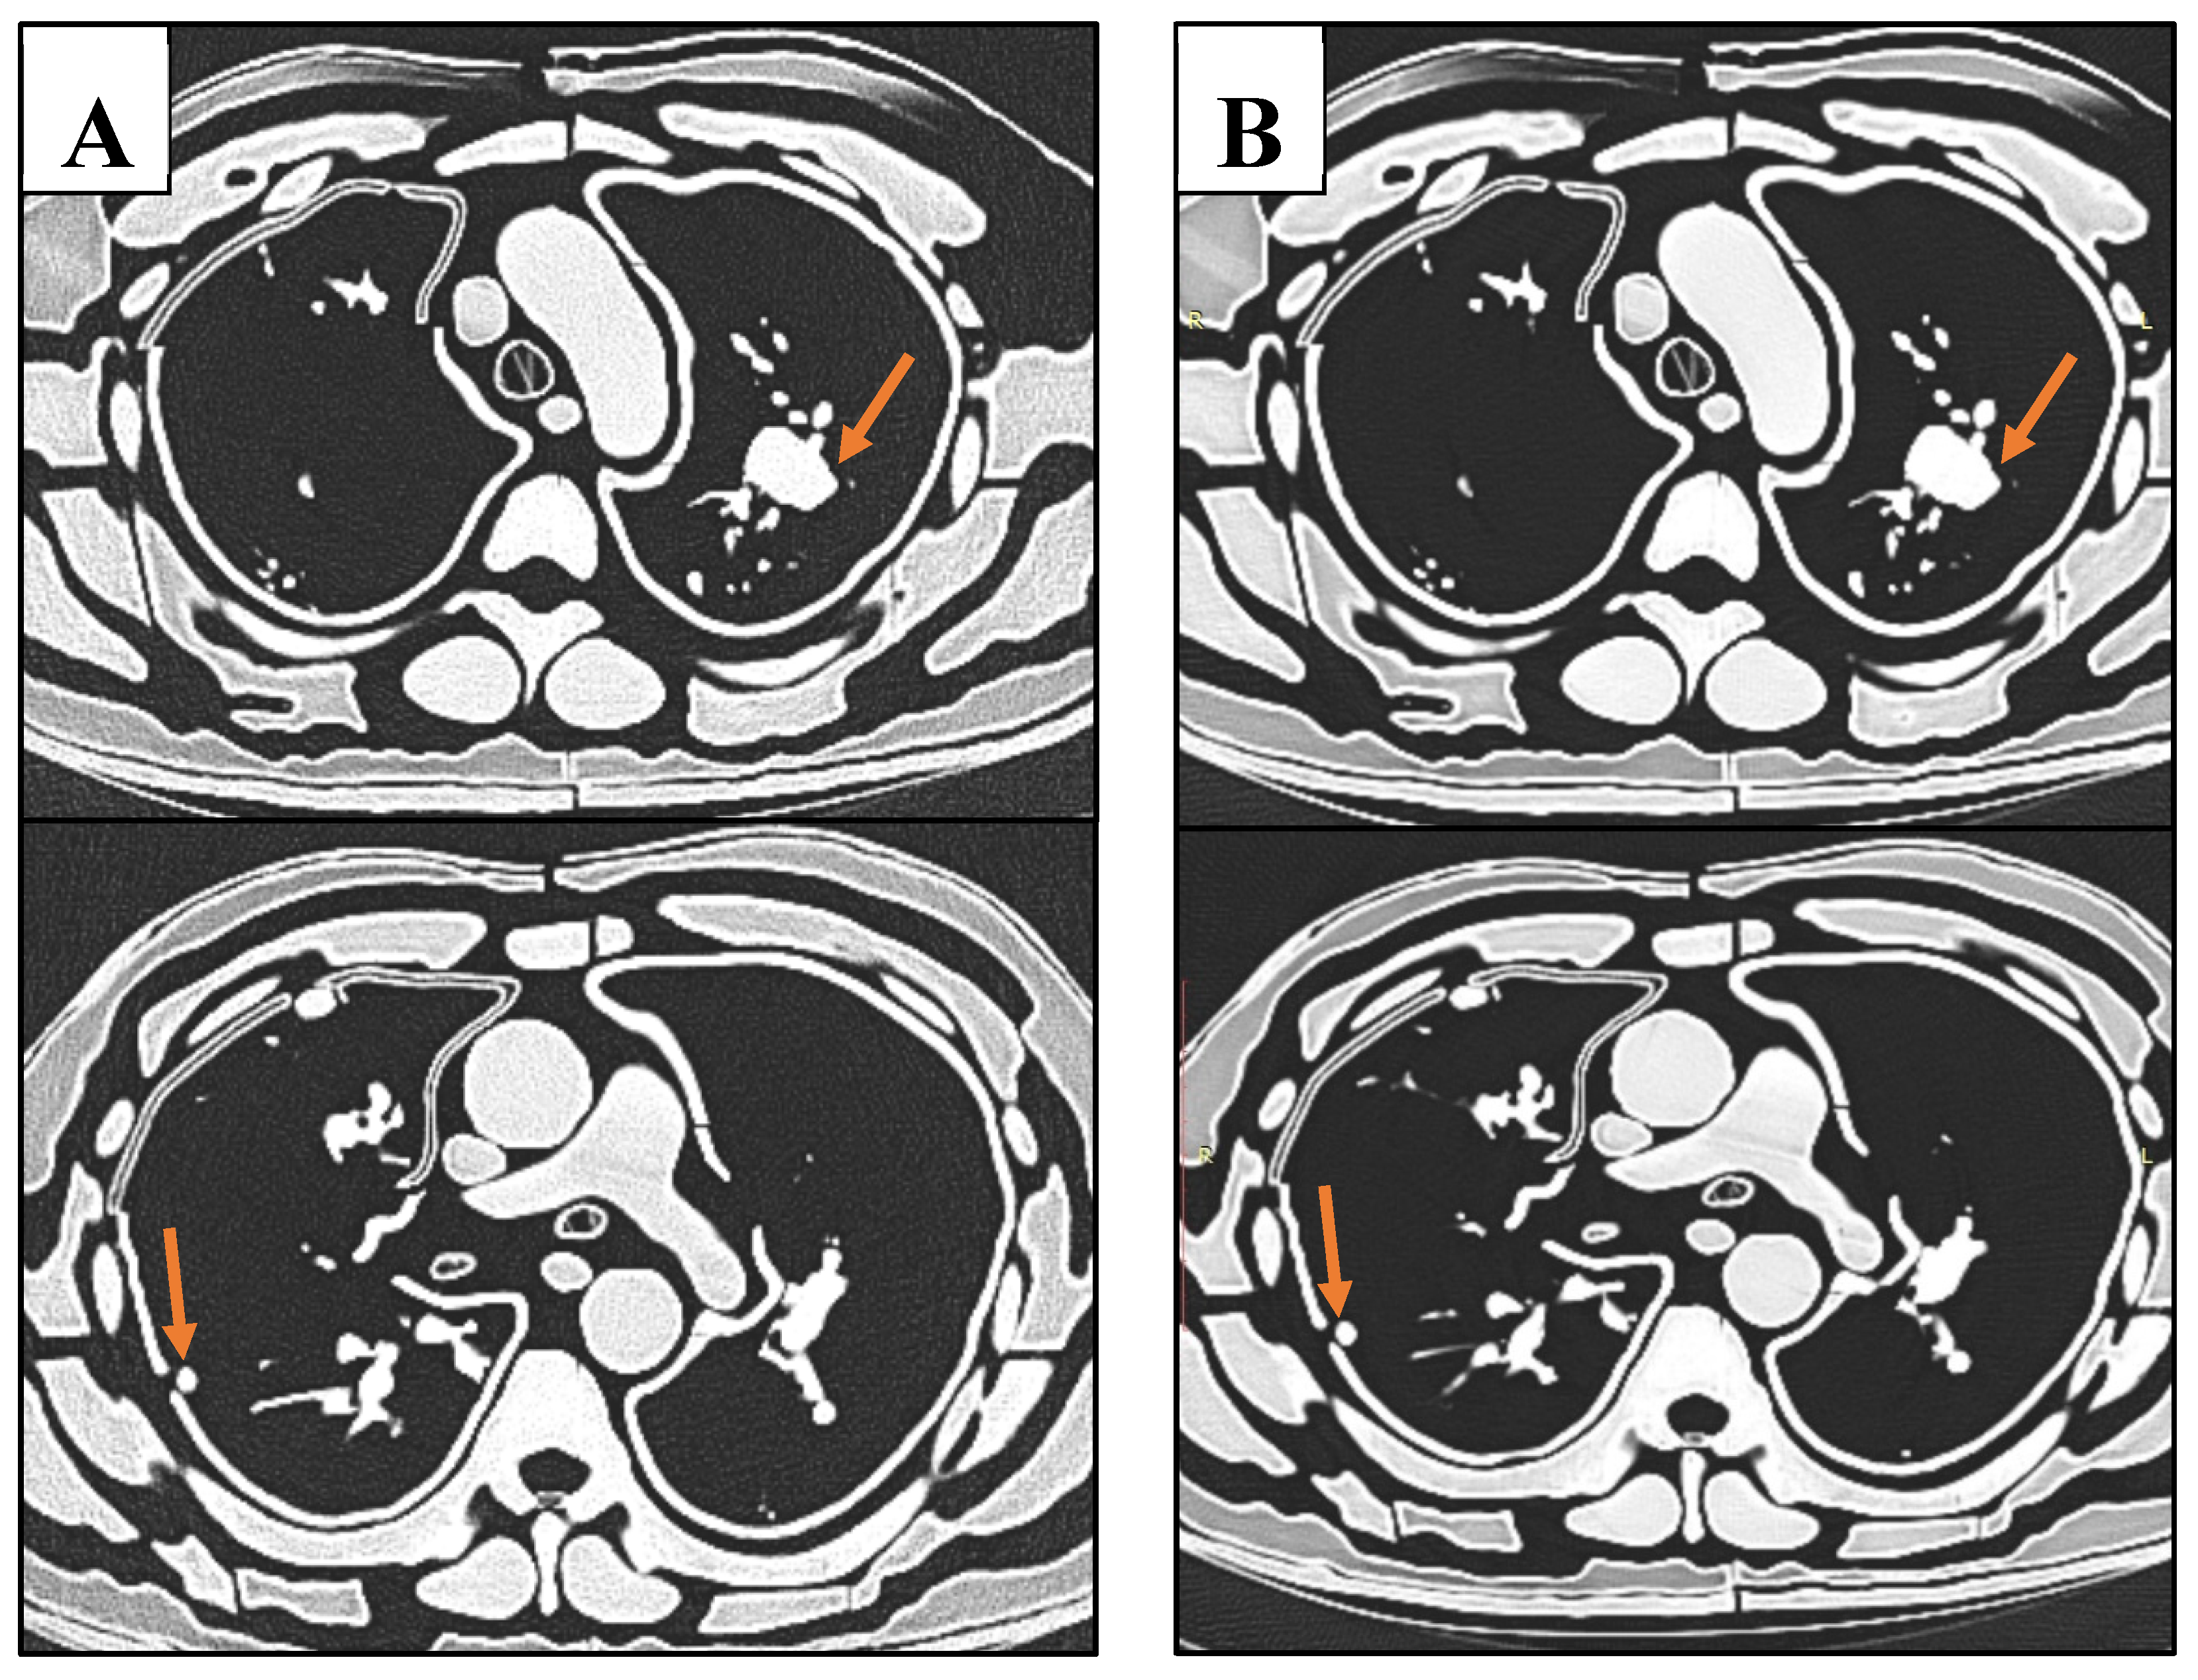

Figure 11. Sample CT slices of phantom. Top row images depict largest nodule. Bottom row images depict smallest lung nodule. A: The lowest dose protocol of 80 kVp, 30 mAs, with slight mottle evident. B: Highest dose protocol of 100 kVp, 352 mAs. Despite increase in noise and hence reduced SNR and CNR, radiologists deemed these images to be diagnostic for detection of lung nodules.

A reduction in kVp and mAs led to a corresponding decrease in effective dose (Table 4, Figure 8). The lowest dose protocol (80kVp and 30mAs with resultant 0.23 mSv) delivered a 96% lower effective dose compared to the standard protocol (100 kVp and 352 mAs with 5.8 mSv). However, this reduction was accompanied by a 72% decrease in SNR and a 69% reduction in CNR (Table 4). Additionally, 81% of the reduction in SNR was explained by the decrease in effective dose, with results demonstrating a significantly strong positive linear correlation between SNR and effective dose (r = 0.92, R2 = 0.81, p<0.001) (Figure 9). Likewise, 87% of the reduction in CNR was explained by the reduction in effective dose, with a significantly strong positive linear correlation (r = 0.93, R2 = 0.87, p<0.001) (Figure 10). Regardless of this diminishing objective assessment of image quality, the subjective image quality scores did not differ between these scans, scoring on average 4/5 representing good diagnostic confidence (κ=-0.398 (95% CI, -0.644 to -0152), p < .002) (Table 4).

Despite the increase in SNR and CNR associated with the reduced effective dose (Figure 9 and Figure 10), this did not affect the subjective visual perception of lung nodules by the radiologists. This affirms the ability and responsibility of radiographers to reduce radiation exposures in order to limit dose to patients, regardless of degradation to image quality, as long as the diagnostic capacity is maintained [54]. Lowering radiation dose is feasible for lung cancer screening due to the high intrinsic contrast between air and pulmonary structures [15]. Iranmakani et al. [55] suggests that clinicians may be hesitant to reduce exposure parameters to ultra-low levels, despite feasibility of producing acceptable image quality with such low radiation levels. Future studies should explore further reductions in kVp and mAs to establish the threshold where noise begins to interfere with diagnostic ability.